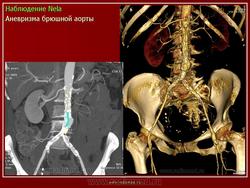

Аневризмы брюшной аорты